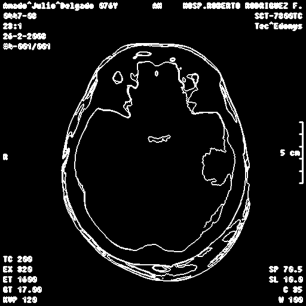

An example of an applications of our proposed strategy to a medical image is shown in Figure 7. In this case, we used different values of and in the . This is a preliminary result. A deeper paper about these results will be published.